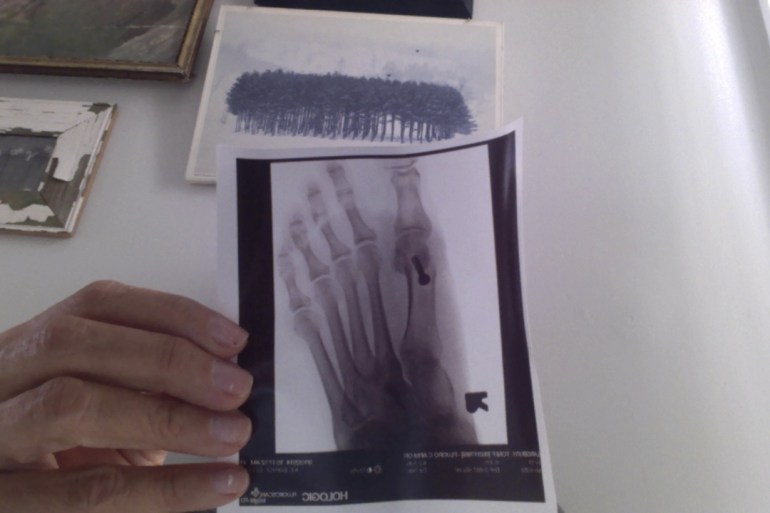

Reporting here on day 8. I have been taking my stupid, heavy, big and clunky boot off and giving my poor little foot a breather every few hours, and yesterday, while it was off, graceful gal that I am, I bumped my big toe on a chair in my den, which hurt, and of course, practically freaked me out of my Lululemon yoga pants (yes, I still wear them, and no, I’m not really proud of myself, but yes they are the best yoga pants for slimming and sucking in your fat, so while they insult my principles as a company, I have my priorities (my fat ass) and that is that). Anyway, it seemed to hurt in the area formerly known as “the bunion,” all day, but really only when I walked on it. I am worried that maybe I shook something out of place, like the hardware in there. I was half expecting to wake up with the screw that is now holding the bone together, rolling around my bed. Don’t you love my fertile and colorful imagination? Anyway, if you’re praying for anything today, throw a line in about my foot health, wouldja? I’d appreciate a novena, or like, whatever you got.